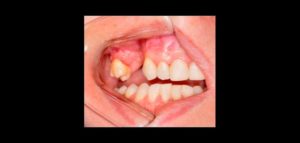

La interrupción en el proceso de odontogénesis da como resultado un diente supernumerario. Esto puede ocurrir por la división del órgano del esmalte o por

El autotransplante es el reposicionamiento de un diente autógeno que ya erupcionó, que esta erupcionando o que no ha erupcionado, de un sitio a otro